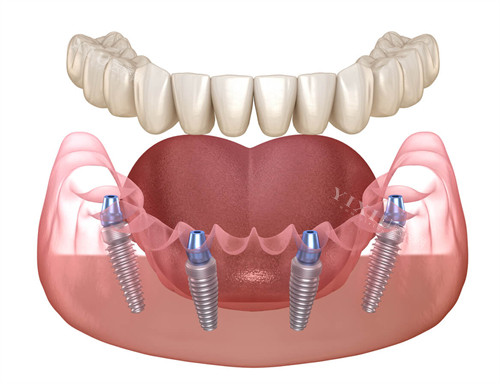

牙槽骨就像种树所需的土壤,土少树就立不住,种植牙也是如此。牙槽骨薄会使种植体无法稳固,骨量不足还会增加种植失败的风险。不过,这并不意味着牙槽骨薄就肯定不能种植牙。如果牙槽骨薄的情况不是很重的,可以采用一些特殊的方法和技术来解决。比如进行骨加高或骨外植入等牙槽骨增加手术,通过移植自体骨或使用人工骨等材料来增加口腔骨量,以便稳定种植牙种植体。但如果牙槽骨过薄,可能会导致种植牙的固定力不足,牙种植失败或者牙齿移位的风险增加,此时可能需要考虑其他替代方案,如固定义齿或活动义齿等。

如果牙槽骨薄的情况较为重的,就需要接受特色治疗。比如植骨手术,这是一种常见且有效的方法。植骨就是通过取自体骨或使用人造骨,增加骨量,满足种植牙要求。具体方法包括自体骨植入、人工骨植入和自体骨与人工骨混合植入。其中,人工骨粉因其无需损伤自体取骨且骨吸收速度慢而被广泛应用。不过,植骨手术也意味着额外的费用和时间成本,一般 1 克人工骨粉上千元,且手术至少需要 3 个月的修复期。对于因牙齿拥挤导致的牙槽骨薄,还可以通过牙齿矫正的方式,调整牙齿排列,改善局部牙槽骨的压力,从而促进牙槽骨的生长发育。

曾经有一位患者,长期牙齿缺失,导致牙槽骨重的变薄,原本想进行种植牙修复,但因骨量不足而面临困境。后来,医生为他制定了植骨方案,采用人工骨粉进行骨增量手术。经过 3 个月的修复期,再次进行种植牙手术,成功种上了牙齿,修复了正常的咀嚼功能。这个病例充分说明,即使牙槽骨薄,通过合适的治疗方法,依然可以解决牙齿修复的问题。